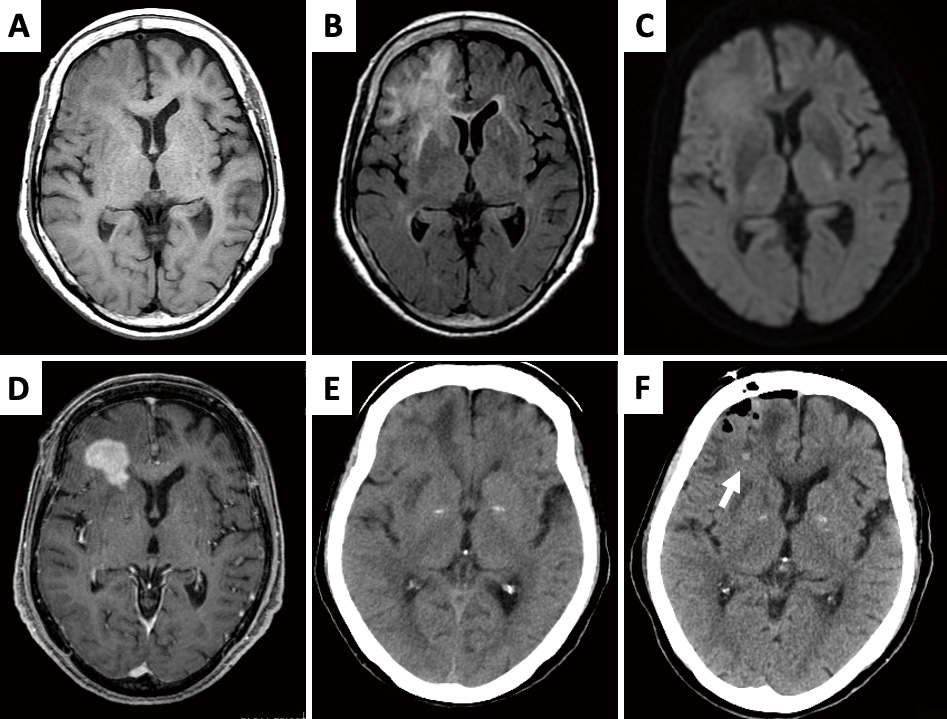

An 84-year-old female presented to our hospital with a gradual, progressive cognitive decline over the past 6 months, without any associated cranial symptoms or paresis. Her Glasgow Coma Scale (GCS) score was 15 (E4V5M6). Imaging revealed a tumor in the right frontal lobe, showing slight hypointensity on T1-weighted imaging (Fig. 1A), hyperintensity on T2-weighted imaging (Fig. 1B), mild hyperintensity on diffusion-weighted imaging (Fig. 1C), and uniform enhancement after gadolinium-diethylenetriamine pentaacetic acid administration (Fig. 1D). No other tumorous lesions were detected on full-body scanning. Blood tests showed tumor marker levels of 1.5 ng/mL for carcinoembryonic Antigen and 305 U/mL for soluble interleukin-2 receptor. A suspected diagnosis of primary CNS lymphoma led to a navigation-guided needle brain biopsy, with samples taken from the tumor's center (Fig. 1E, F). The intraoperative diagnosis was high-grade glioma, and the specimen obtained was sufficient for histopathological diagnosis. No new neurological deficits developed post-operatively. Due to the patient's poor general condition and deteriorated consciousness (GCS score of 15, Mini-Mental State Examination score of 27, and Frontal Assessment Battery score of 11), both she and her family opted against further aggressive treatment. Despite concerns about post-operative deterioration, we were unable to monitor her clinical progression, and she passed away 4 months after surgery due to tumor progression. No autopsy was performed. Informed consent was obtained prior to submission, as this case report contains protected health and identification information.

MRI revealed the presence of a tumor in the right frontal robe. (A) The lesion was slightly hypointense on T1WI. (B) Hyperintense on T2WI. (C) Slightly hyperintense on DWI. (D) Uniformly enhanced following administration of gadolinium-diethylenetriamine pentaacetic acid. (E) Plain CT showed an isodense tumor with edema. (F, arrow) A hemorrhagic point revealing the site of biopsy was identified in post-operative CT.

CT: computed tomography; DWI: diffusion-weighted imaging; MRI: magnetic resonance imaging; T1WI: T1-weighted imaging; T2WI: T2-weighted imaging